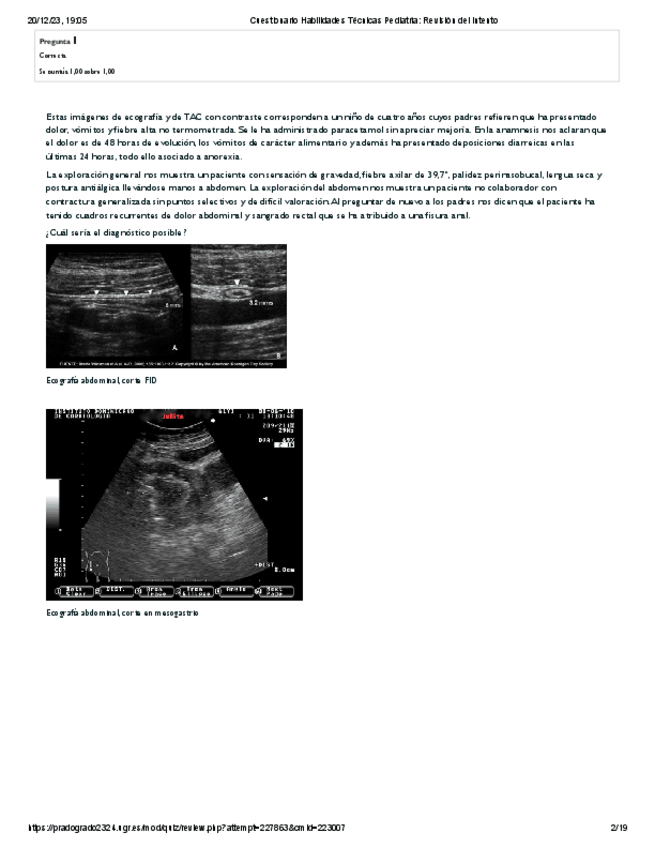

He publicado nuevos examenes de 5º PEDIATRÍA Y CIRUGÍA PEDIÁTRICA I: Cuestionario-Habilidades-Tecnicas-Pediatria-Revision-del-intento.pdf

19 páginas